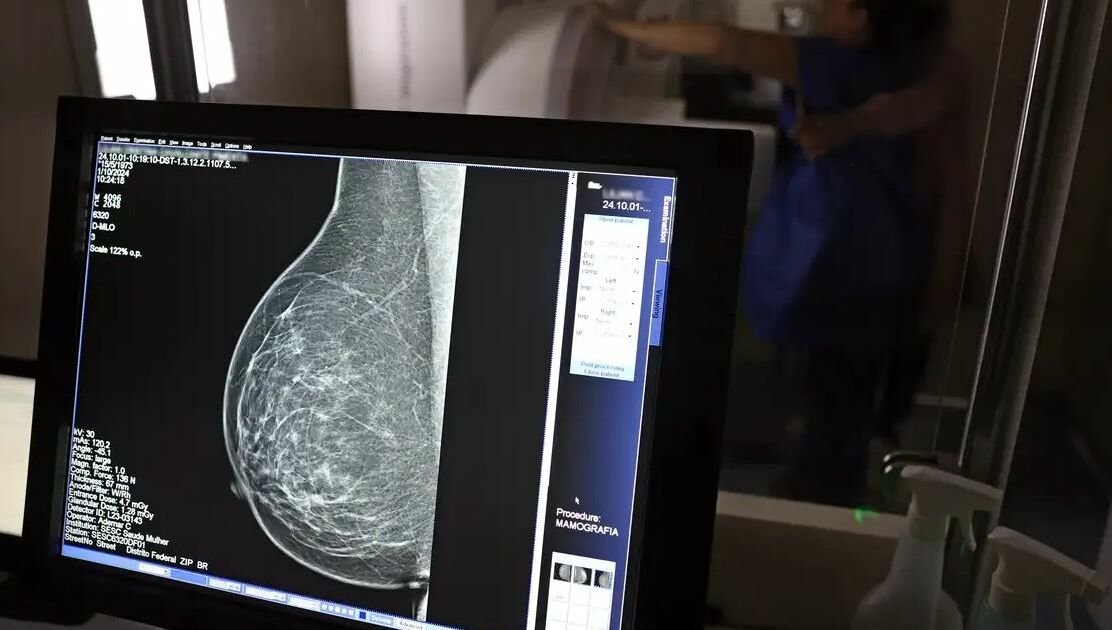

Uma nova legislação, sancionada pelo presidente Luiz Inácio Lula da Silva e publicada no Diário Oficial da União, fortalece os direitos dos trabalhadores regidos pela Consolidação das Leis do Trabalho (CLT) em relação à saúde preventiva. A Lei 15.377, publicada em 6 de novembro de 2023, permite que esses trabalhadores se afastem por até três dias por ano para realizar exames preventivos de câncer, com a ressalva de que os dias de afastamento terão desconto no salário. Essa medida já estava prevista na CLT desde 2018, mas a nova lei traz importantes inovações.

Uma das principais mudanças é a exigência para que as empresas informem seus empregados sobre esse direito, além de conscientizá-los sobre campanhas de vacinação contra o HPV e sobre a importância do acesso a serviços de diagnóstico para diferentes tipos de câncer, incluindo mama, próstata e colo do útero. Essa divulgação é uma tentativa de aumentar a conscientização sobre a saúde preventiva e garantir que os trabalhadores conheçam seus direitos.

Outro aspecto significativo da nova lei é a ampliação do direito de afastamento para incluir exames preventivos relacionados ao HPV, além dos já estabelecidos para câncer. Isso demonstra uma preocupação crescente com a saúde dos trabalhadores, reconhecendo a importância de diagnósticos precoces e prevenção de doenças que podem ser fatais se não tratadas a tempo.